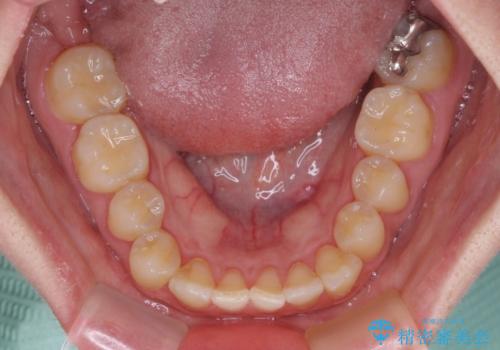

- 前歯の反対咬合を気にして来院された患者様です。

当院にて同様の咬み合わせを治療した方からのご紹介ということもあり、ご紹介者と同じワイヤー矯正で早めに治療を終えることを希望されました。

骨格的に下顎が前方に位置していましたが、歯列矯正で改善できると判断し、ワイヤー装置にて矯正治療を行うこととしました。